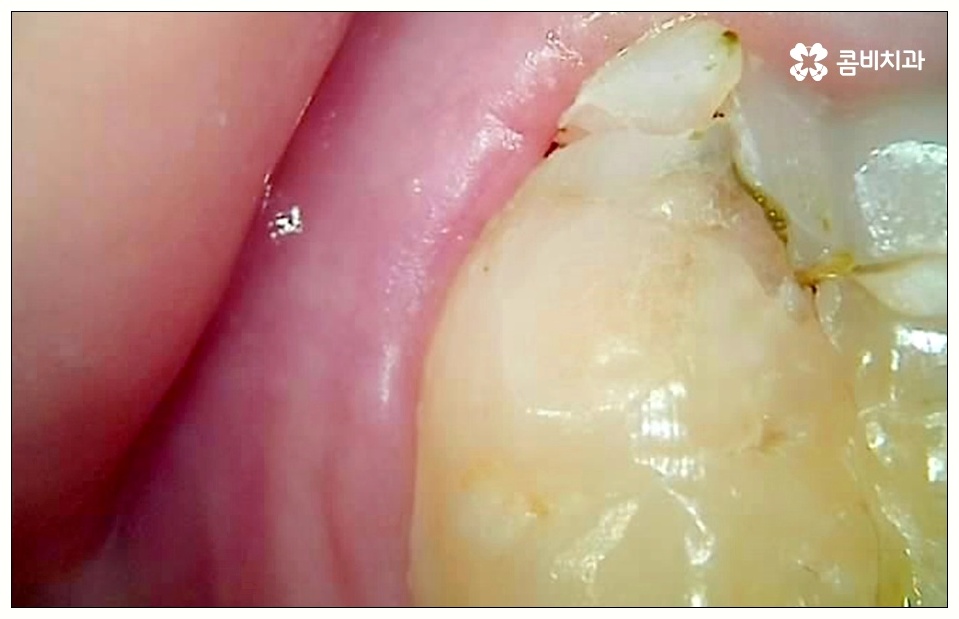

하지만 꼭 발치 처치를 받아야 하는 사랑니도 있는데 그 중 대표적인 것이 바로 어금니 사이 충치 를 유발한 경우로, 비스듬하게 나온 사랑니가 앞의 어금니를 밀면서 압박을 주고 옆면에 충치를 일으키는 등 손상시키고 있다면 늦기 전에 발치 처치를 받으실 필요가 있습니다.

이 때 어금니 뒤쪽으로 비스듬하게 사랑니가 자리를 잡으면 부분적으로 맹출이 되면서 치아 사이에 좁은 틈새가 만들어져 여러 가지 부산물들이 끼기 쉬워지는 반면 칫솔질 등 관리는 더욱 어려워지기 때문에 구강 질환 발생률이 높아질 수 있어요.

특히 어금니 사이 충치 는 눈에 잘 보이지 않을 뿐만 아니라 어느 정도 진행이 될 때까지 통증이 크지 않기 때문에 치료시기를 놓치게 되는 경우가 많이 있는데요.

환자분들께서 알아차리는 것이 어려운 경우가 많으니 이러한 어금니 사이 충치 에 대처하기 위해서 평상시에 통증이 없더라도 정기적으로 치과에 내원하셔서 정밀 검진 및 스케일링 처치를 받아주시는 습관을 가지시면 구강 건강을 유지 관리하는 데 더욱 바람직할 수 있어요.